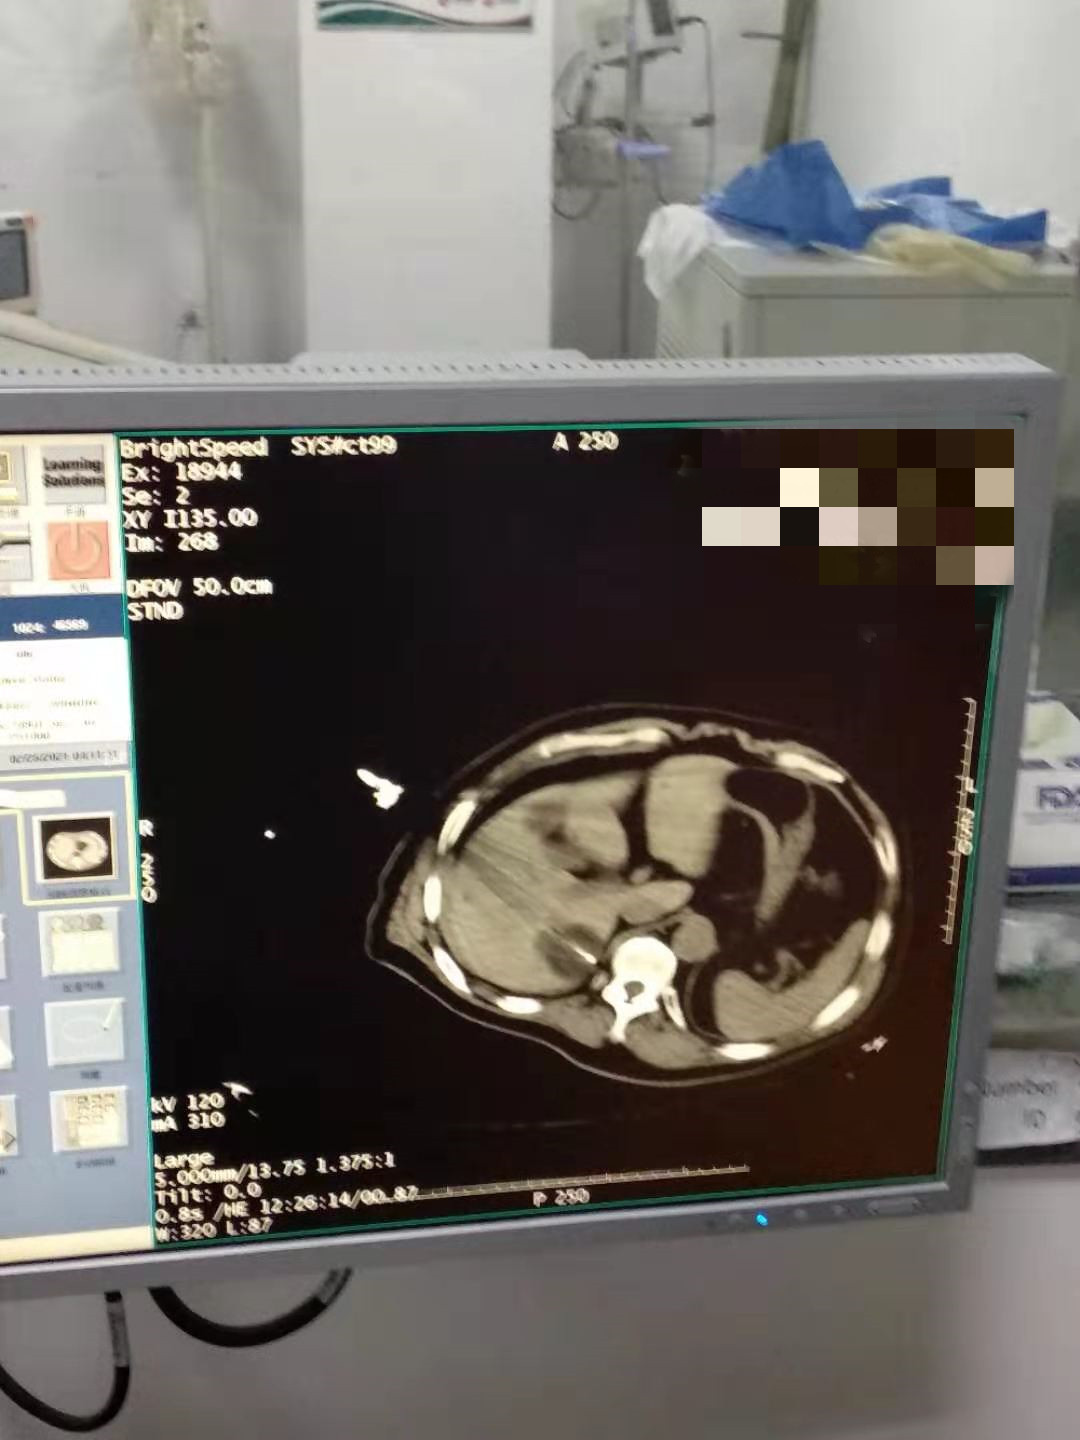

2021年2月份肝部氩氦刀手术